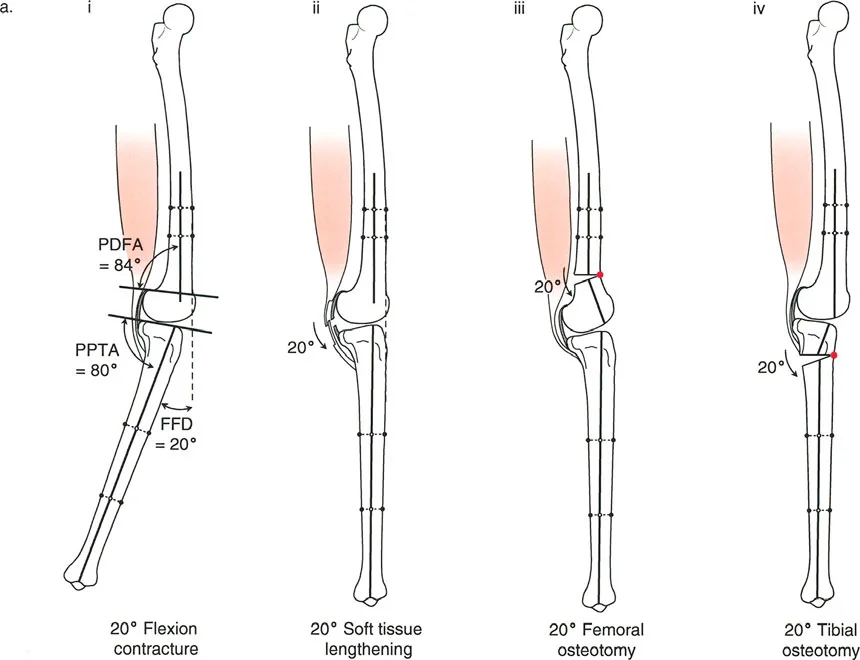

تصحيح تحدد حركة الركبة (Flexion Deformity - FFD)

تحدُّد حركة الركبة هو عدم القدرة على مد الركبة بالكامل. يمكن أن يكون سببه عظميًا أو ناتجًا عن تقلص في الأنسجة الرخوة.

- التشخيص الدقيق: يجب تحديد ما إذا كان تحدد الحركة ناتجًا عن تشوه عظمي (تقوس أمامي في الفخذ أو الساق) أو تقلص في الأنسجة الرخوة (الأوتار الخلفية، محفظة المفصل).

- قطع العظم التمديدي (Extension Osteotomy):

- إذا كان التشوه عظميًا، يتم إجراء قطع عظم تمديدي في عظم الفخذ أو الساق لتصحيح التقوس.

- الأستاذ الدكتور محمد هطيف يؤكد على أهمية عدم تصحيح الساق بأكثر من 90 درجة PPTA لتجنب فقدان الميل الخلفي الطبيعي للساق.

- تحرير الأنسجة الرخوة (Soft Tissue Release):

- إذا كان السبب هو تقلص الأنسجة الرخوة، فقد يتم إجراء إطالة للأوتار أو تحرير لمحفظة المفصل.

تصحيح الركبة الارتدادية (Recurvatum Deformity - Hyperextension)

الركبة الارتدادية هي فرط البسط في الركبة. غالبًا ما تكون غير مصحوبة بأعراض في الأشخاص ذوي العضلات السليمة، ولكنها قد تسبب مشاكل في حالات ضعف العضلات أو التشوهات العظمية.

- التشخيص: يجب تحديد ما إذا كانت الارتدادية عظمية (تقوس خلفي في الفخذ أو الساق) أو ناتجة عن رخاوة في الأنسجة الرخوة أو ضعف عضلي.

- قطع العظم الانثنائي (Flexion Osteotomy):

- إذا كان التشوه عظميًا (تقوس خلفي)، يتم إجراء قطع عظم انثنائي في عظم الفخذ أو الساق لتصحيح الارتدادية.

- الأستاذ الدكتور محمد هطيف يشدد على أهمية عدم استخدام قطع عظم الفخذ الانثنائي لتصحيح ارتدادية الساق، والعكس صحيح، لتجنب الانزلاق الخلفي أو الأمامي للركبة.

- اعتبارات خاصة: في المرضى الذين يعانون من ضعف عضلي (مثل شلل الأطفال)، قد يحتاج التصحيح إلى فرط تصحيح بسيط (overcorrection) إلى وضعية انثناء لضمان ثبات الركبة ومنع فرط البسط غير المتحكم فيه.